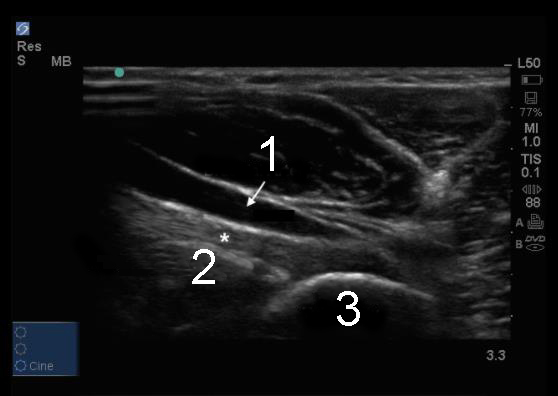

Elbow Distal Bicep Tendon at Radial Tuberosity Image

1. Brachial Artery

2. Distal Biceps Tendon

3. Radial Tuberosity